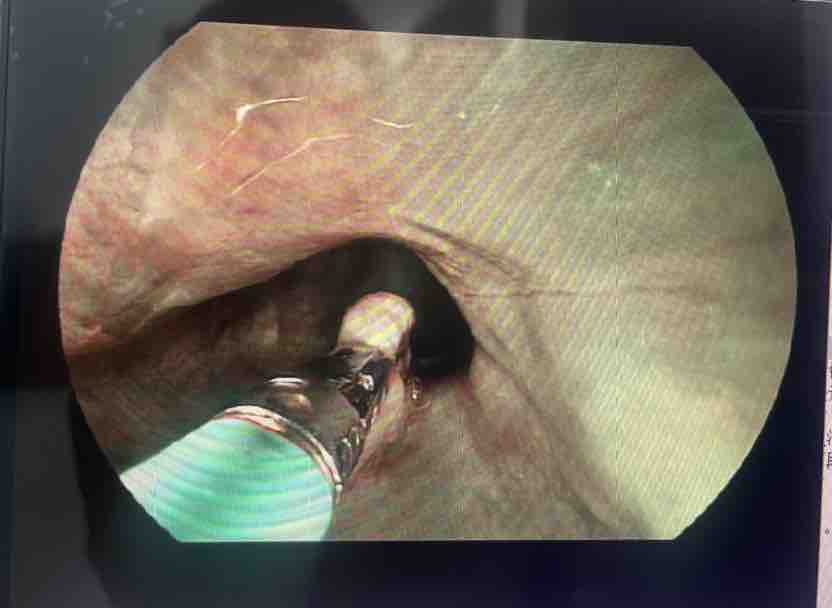

近日,古蔺县中医医院肺病·脾胃病·内分泌科开展1例内镜下息肉切除术。患者张某(化名),女,48岁,因“反复剑突下疼痛1年余。”来医院就诊。经胃镜检查发现,其胃体内存在多发性息肉,其中可见3枚大小约3-6mm的息肉样隆起,胃体前壁见两条线性虫体蠕动,经与家属充分沟通后,为其施行了内镜下胃息肉切除术。手术过程中,通过内镜将专用器械送至病变部位,精准地切除了所有可见息肉,并进行胃窦前壁、胃体交界处病理活检。术后患者恢复良好,无明显不适感。术后病理证实为:炎性息肉、考虑慢性非萎缩性胃炎。

患者胃镜术前术后对比图片